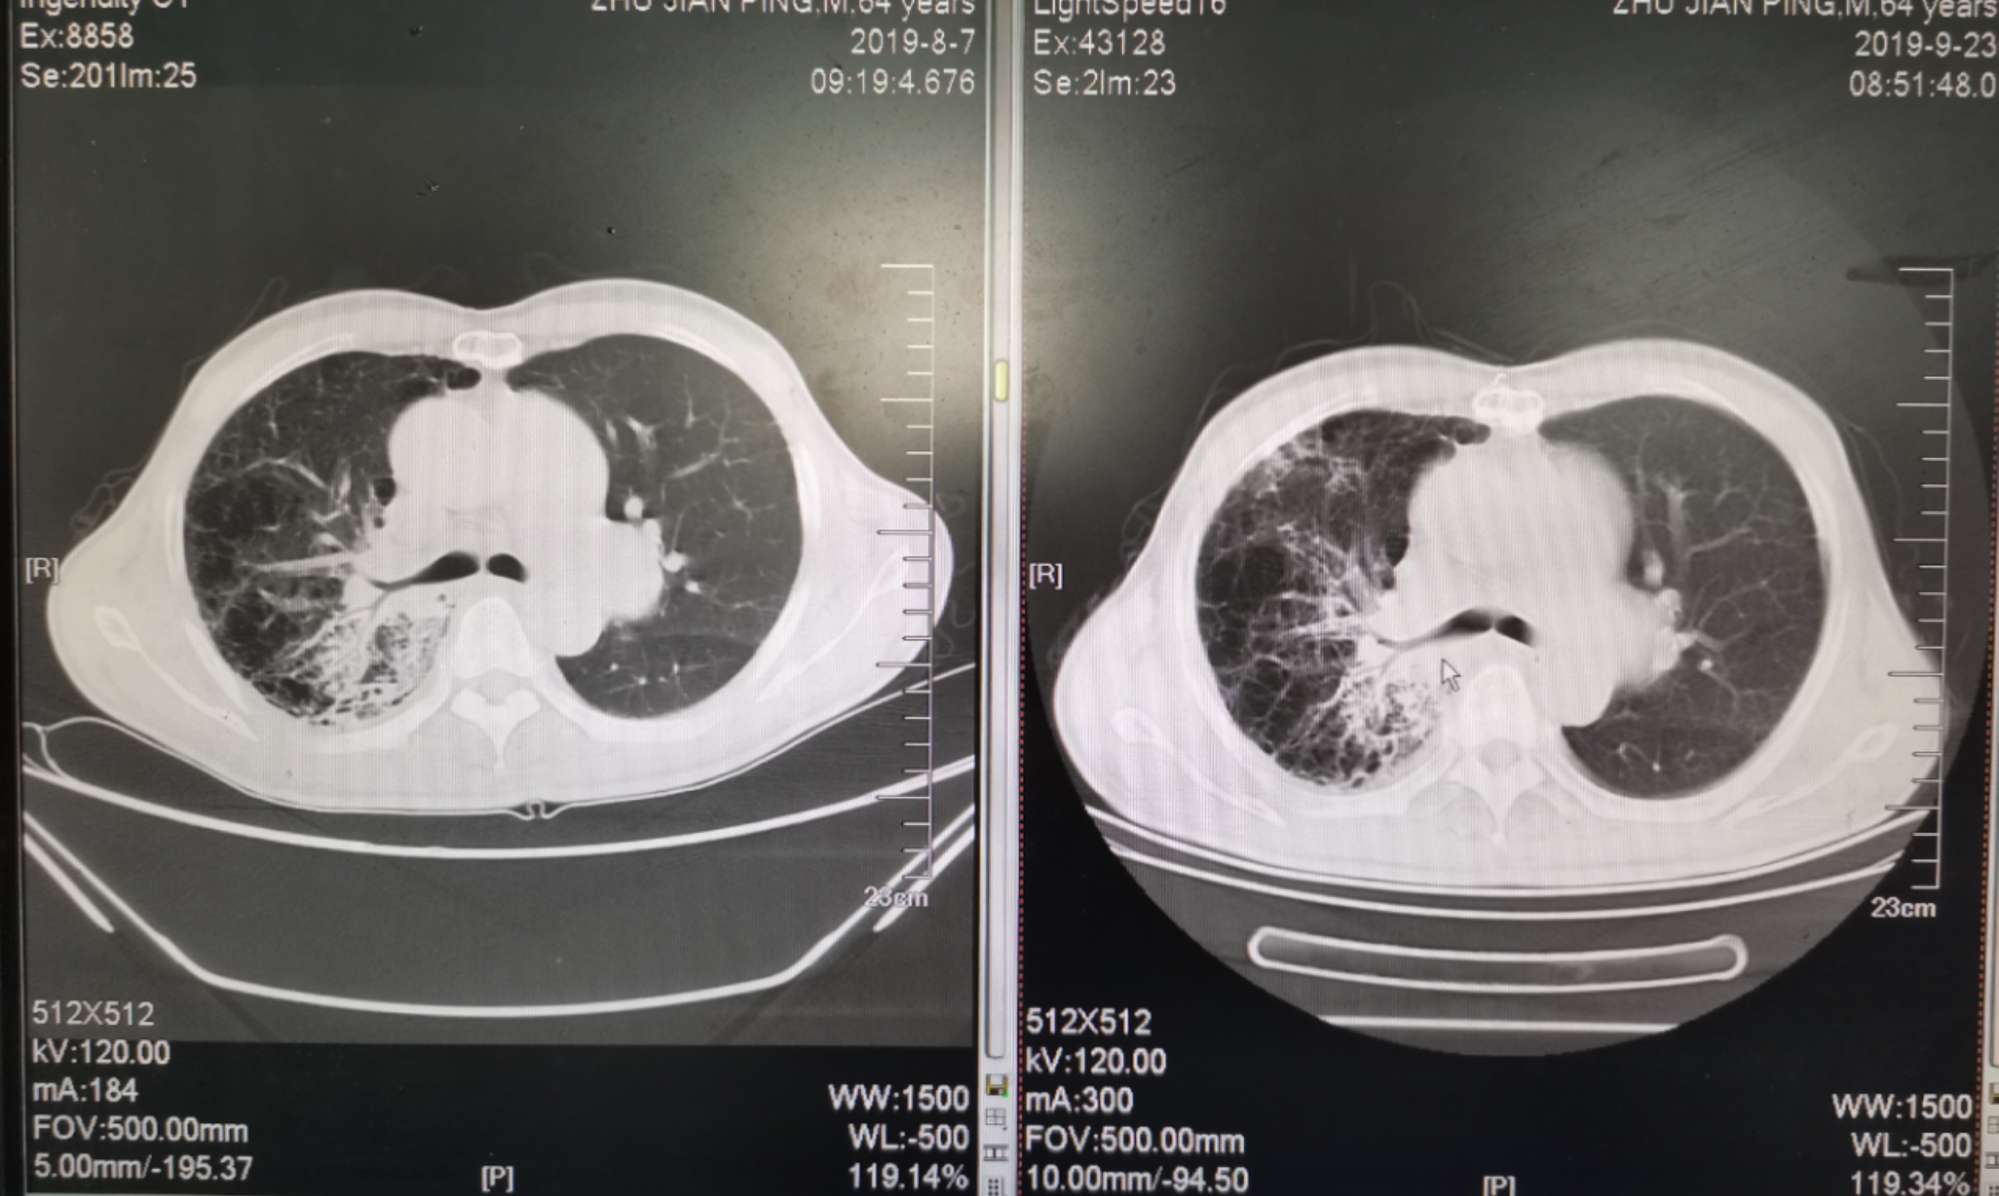

二化联合一k后复查ct对比

左边是上月化疗前的,右边是昨天拍的,今天上了第二次k药,准备明天第三期化疗。

我自己对着拍的,切面对的不是很准确,但大致上看的出来明显小了。